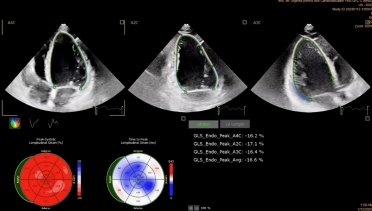

TTE was performed. The LV had a normal size, however, left ventricular ejection fraction (LVEF) was mildly impaired (48%) with mild longitudinal dysfunction (GLS -16,6%). The mitral valve appeared thickened and redundant, with bi-leaflet prolapse and mild regurgitation. MAD was seen, with a length of 4-5mm measured in mid-systole.

Tissue Doppler imaging (TDI) of the lateral wall revealed a second systolic peak, with a velocity of 17cm/s. Through speckle-tracking analysis, a double peak strain pattern is seen on the basal infero-lateral wall (orange arrows).

- Double-peak strain pattern of the basal infero-lateral wall. Recently, double-peak strain showed incremental risk of arrhythmia over fibrosis in patients with MVP, highlighting the interplay between abnormal LV mechanics and arrhythmic events (9).